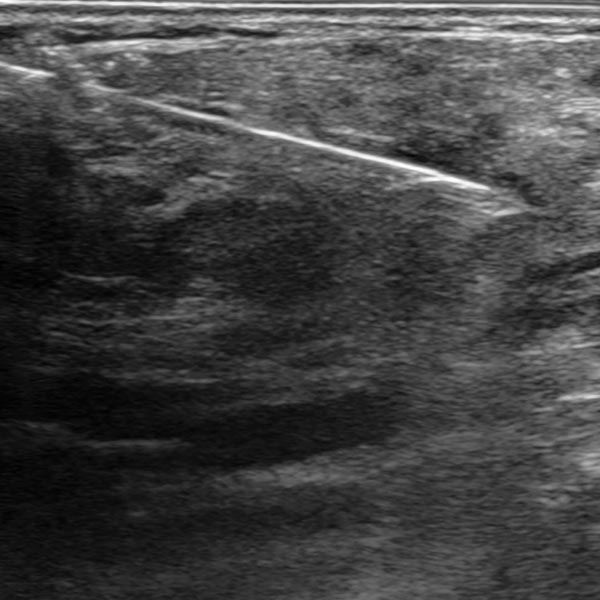

Um die Diagnose trotz der Hinweise auf ein infantiles Hämangiom klar zu sichern, bei differentem Verhalten der kutanen (fast rückgebildet) und der subkutanen Anteile (Wiedervergrößerung), wurde noch eine histopathologische Sicherung mittels Stanzbiopsie durchgeführt. Das Ultraschallbild zeigt die Biopsiepistolennadel innerhalb des Tumors am Oberarm.

Das histopathologische Übersichtsbild (40-fache Vergrößerung; HE-Färbung) des Stanzzylinders der Läsion zeigt Skelettmuskulatur, die diffus durchsetzt ist durch lobulär angeordnete, kapilläre Proliferate sowie einzelne Fettzellen (weiße, rundliche große Zellen), die ein Hinweis auf eine bereits stattfindende Involution sind.